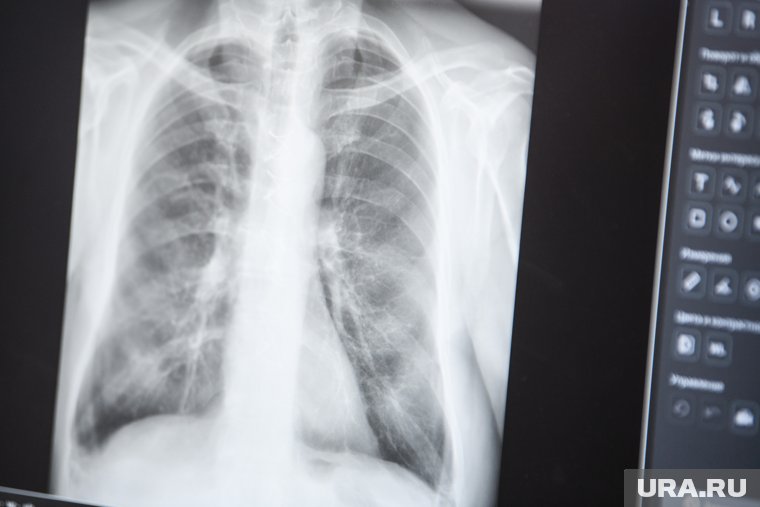

День борьбы с раком легкого

Каждый год 1 августа проводится Всемирный день борьбы с раком легкого, цель которого — привлечь внимание к одной из самых опасных форм онкологии, рассказать о факторах риска, методах профилактики и новых подходах к лечению.

Рак легкого занимает первое место среди причин смертности от онкозаболеваний. В начале XX века болезнь была редкостью, но сегодня на нее приходится около 13% всех злокачественных опухолей. В России ежегодно выявляют более 50 тысяч новых случаев, и в 70% из них диагноз ставят уже на поздних стадиях, когда лечение менее эффективно.

Основные причины — курение, вредные производства и плохая экология. Однако благодаря развитию медицины появляются эффективные методы лечения, такие как иммунотерапия. Важную роль также играют флюорография и рентген, позволяющие выявить опухоль на раннем этапе.

В этот день по всему миру проходят просветительские акции, медицинские конференции и встречи с онкологами. Это напоминание о важности профилактики, своевременной диагностики и заботы о здоровье.